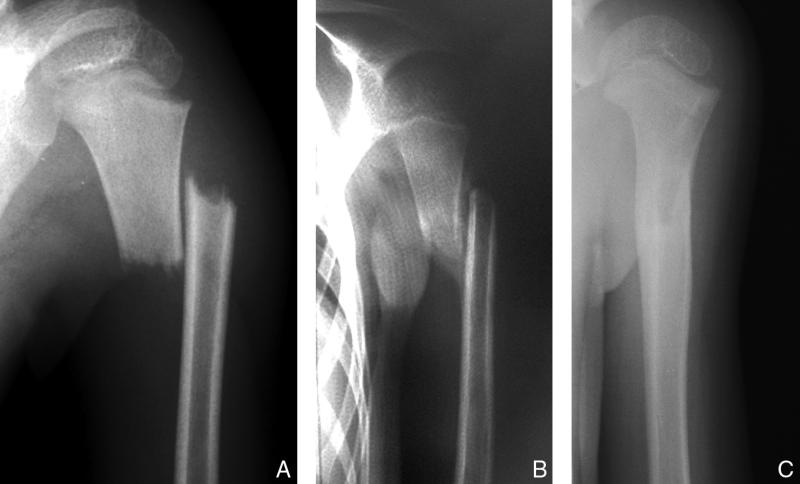

Fig. 71.6.   Remodelage périosté.

Remodelage périosté.

Radiographie du bras. Garçon de 5 ans présentant une fracture bicorticale déplacée en « baïonnette » diaphysaire de l’humérus gauche (A).

Cette fracture est immobilisée coude au corps sans réduction. Au 34e jour, le cal est bien visible (B).

Au 4e mois post-traumatique, le remodelage de la fracture est presque complet (C).